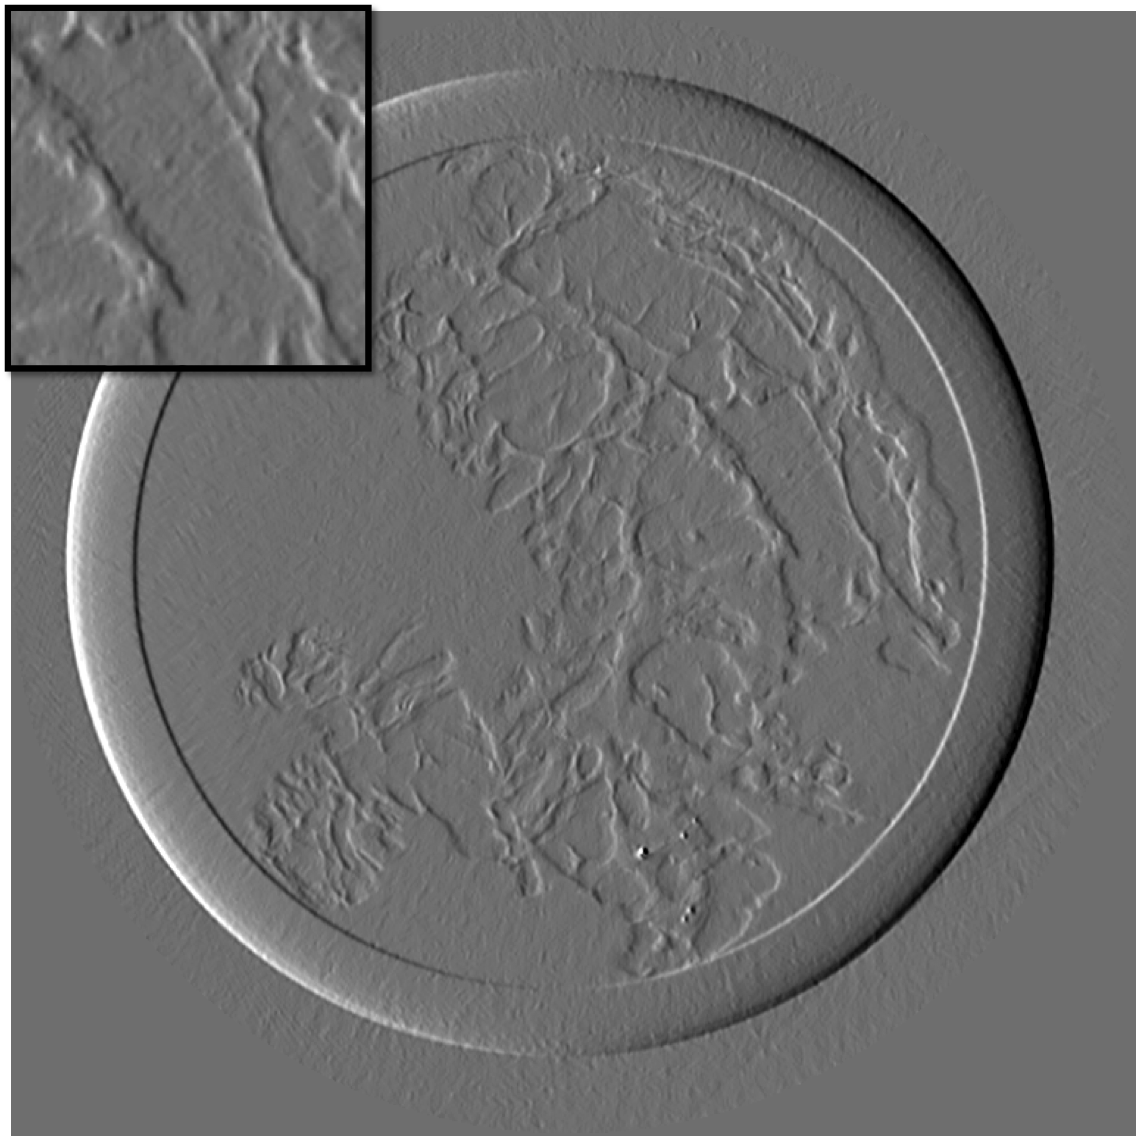

Figure 10 is the reconstruction for a pixels slice, using only 200 projections over the 1000 available. The upper left square is a zoom in the region marked in sub figure 10. The right column is the reconstruction with our method for X and Y components, while the left column is reconstructed with standard filtered back-projection using all 1000 available projections. Using our method we can still generate a high quality image with only one fifth of the projections which would be otherwise necessary to generate a high quality reconstruction with the standard FBP method. Visually the difference between the FBP results obtained with full data set and our method with a five-fold reduction of data is barely noticeable. The different borders of structures like skin layers, fatty tissues, and collagen strands are easily identified. The obtained result are very promising and a systematic evaluation for clinical application is under-way. The radiation dose absorbed by the sample during 200 projections is comparable to that of a standard clinical dual view (2D) mammography (3.5mGy).

For an eventual future clinical application of the PCI method it is important to investigate which is the acceptable compromise in terms of low dose and sufficient level of image quality. We need therefore to better explore how the quality of the reconstruction is degraded when we reduce the dose (i.e. number of projections and the acquisition time) further below the standard values. To this end, we performed a reconstruction with only 125 projections and results are shown in the figure III-D for one gradient differential image.

For an eventual future clinical application of the PCI method it is important to investigate which is the acceptable compromise in terms of low dose and sufficient level of image quality. We need therefore to better explore how the quality of the reconstruction is degraded when we reduce the dose (i.e. number of projections and the acquisition time) further below the standard values. To this end, we performed a reconstruction with only 125 projections and results are shown in the figure11. The first column present the result using our method, the second column is the result of reconstruction using FBP algorithm.

If a slightly higher noise level is tolerable, the method may be used with very few projections and thus applied to the screening and diagnosis of human breast cancers with an even lower radiation dose than conventional dual mammography. The results of our reconstruction show an image quality and a capability of discriminating fine structures that are still clinically acceptable. On the contrary, images produced with the standard FBP reconstruction method are very noisy and not diagnostically satisfactory.